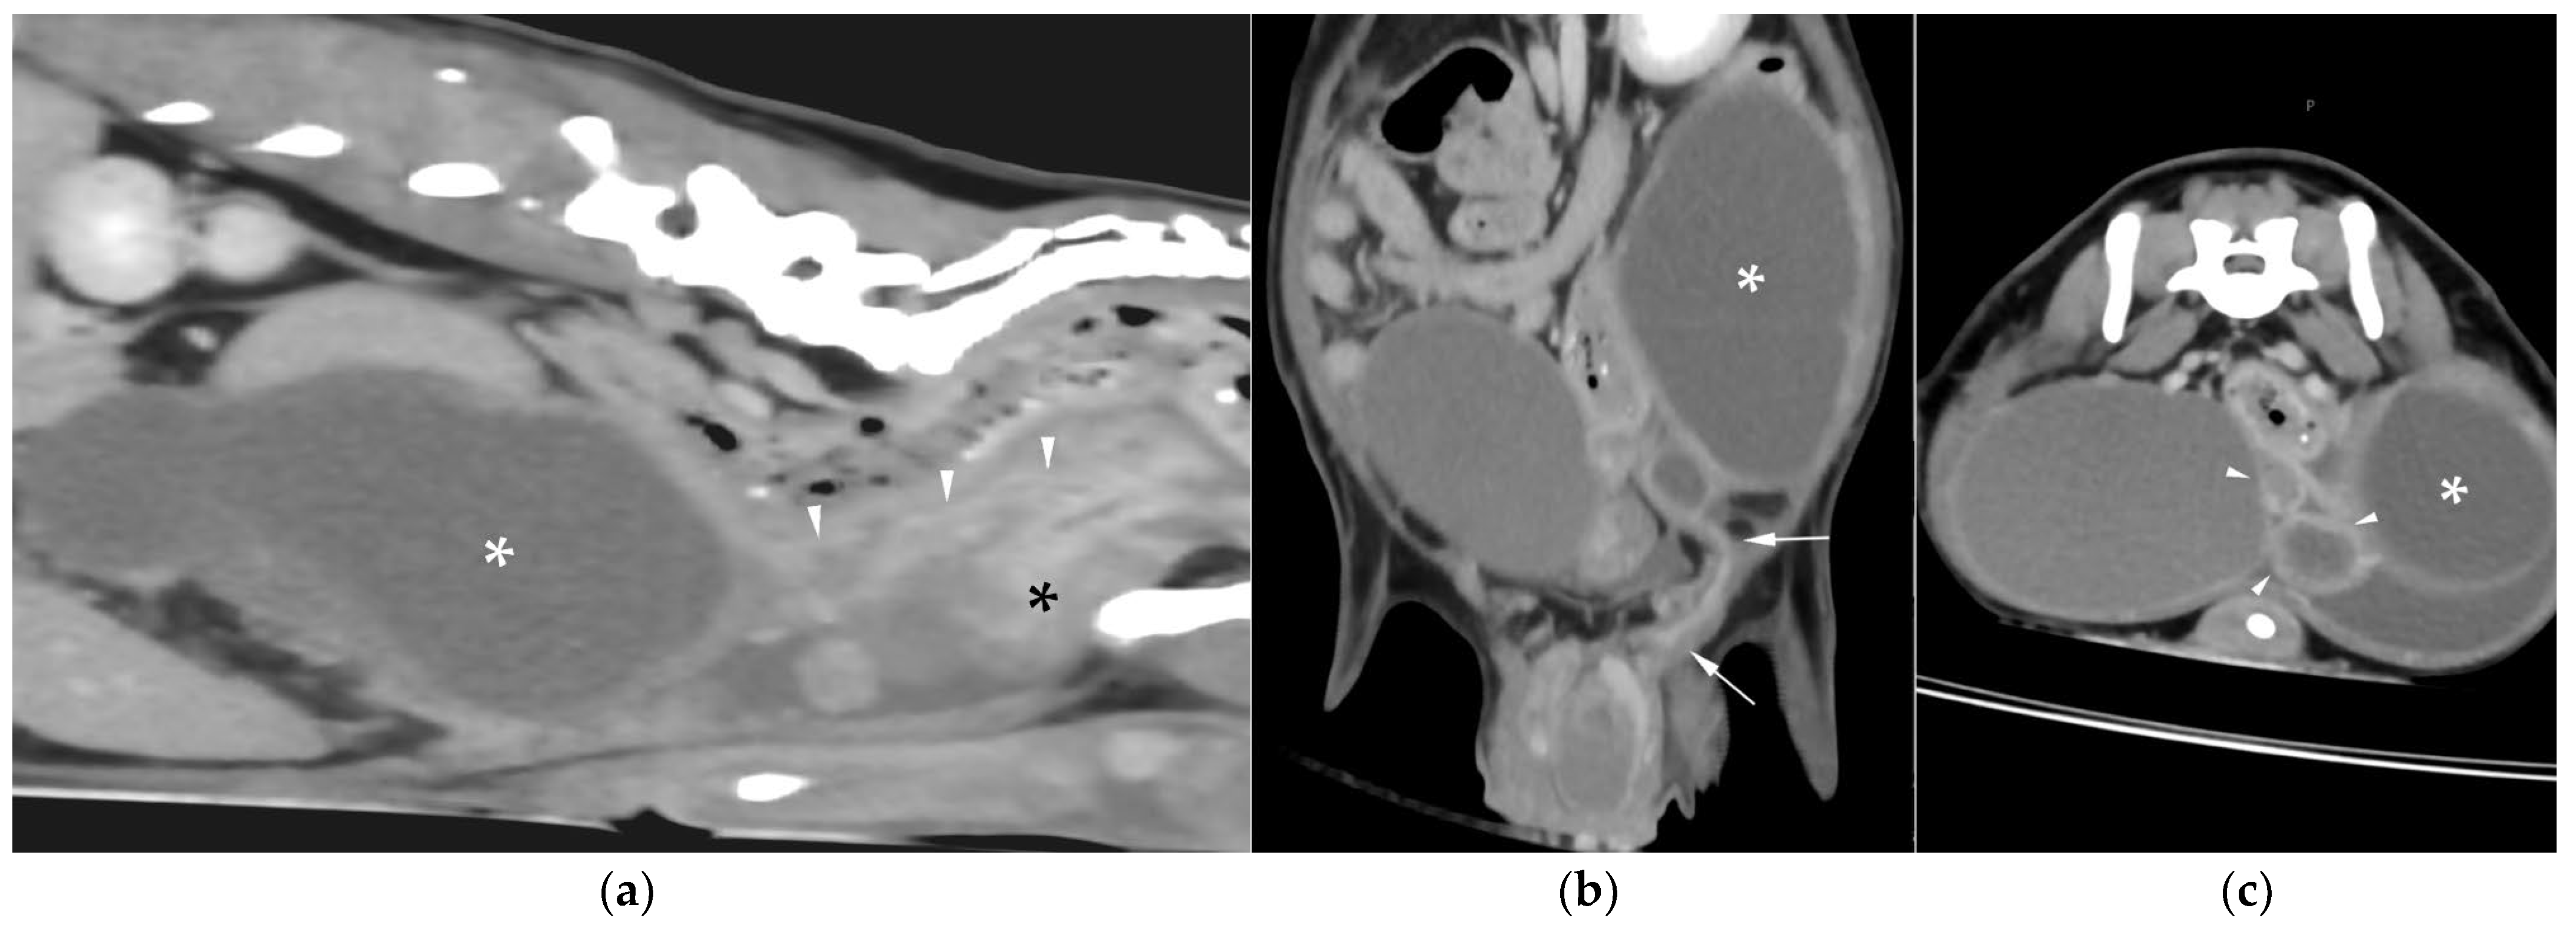

CT revealed a large cavitary structure arising from the craniodorsal aspect of the prostate and extending cranially through the mid-abdomen in each dog (Figure 4a, Figure 5a and Figure 6a). In cases 1 and 2, the structure consisted of a large central cavity, with bilateral horns, coursing caudally through the inguinal rings to each scrotal testis (Figure 4b and Figure 5b). The horns were fluid distended, except for the right horn in case 2, in which no lumen could be identified. In case 3, a Y-shaped bicornuate structure was identified (Figure 6a); the right horn terminated in a cranial peritoneal mass, while the left one ended in the mid-caudal abdomen.

All lesions had thin walls with moderate contrast enhancement, slightly irregularly marginated in cases 2 (Figure 5c) and 3, and smooth in case 1. In cases 1 and 3, moderate dilation involved the entire organ, with a focal mural narrowing resembling a cervix observed at the caudal aspect of the structure (Figure 4a and Figure 6a). In case 2, only minimal dilation of the most caudal portion of the UM was noted (Figure 5a). The luminal content was mildly hyperattenuating (10–20 Hounsfield units) in all cases. It was homogeneous except in the cranial portion of the UM of case 2, where attenuation was slightly higher in the gravity-dependent ventral aspect (20 Hounsfield units) compared with its dorsal aspect (11 Hounsfield units). In case 1, small dorsal bubbles of gas were also noted, likely due to prior drainage at the referring center.

In case 1, both testes were heterogeneous with irregular, ill-defined multifocal lesions after contrast; in case 2, a nodule was present in the left testis. In case 3, in continuation with the cranial end of the right uterine horn and intimately associated with engorged right gonadal vessels, a large, irregular, heterogeneous mass with moderate contrast enhancement was identified, causing a regional mass effect (Figure 6b). No structures compatible with a left gonad were detected in case 3, consistent with the previous unilateral orchiectomy.

Additional findings in all cases included: an enlarged, heterogeneous prostate with small hypoattenuating foci after contrast administration; free peritoneal fluid (moderate in case 2, mild in cases 1 and 3); and iliosacral lymphadenomegaly (moderate in cases 2 and 3, mild in case 1). Enlarged mammary glands and nipples were also noted in case 3.

Figure 4. Computed tomography (CT) of case 1: (a) Slightly oblique longitudinal view showing the UM, extending from the prostate gland (black asterisk), passing dorsally to the urinary bladder, at which level a cervix-like mural narrowing (arrowheads) is identified, with a more distended portion of the UM (white asterisk) cranial to it; (b) Slightly oblique dorsal view showing the distended UM (asterisk) cranial to the contrast-filled urinary bladder, with the uterine horns coursing caudally on both sides and running through the inguinal rings (arrows).

Figure 5. CT of case 2: (a) Slightly oblique longitudinal view showing the UM, extending from the prostate gland (black asterisk), not distended at this level (white arrowheads), through the mid-caudal abdomen, where a more distended portion of the UM (white asterisk) is identified. Ventral to it, there is a scant volume of peritoneal free fluid; (b) Dorsal view showing the UM (asterisk) on the left, with caudal extension of the left uterine horn through the inguinal ring into the scrotum (arrows), and the urinary bladder positioned on the right; (c) Transverse view depicting the urinary bladder on the right and three transverse sections of the UM (asterisk) on its left, surrounded by free peritoneal fluid. The two UM sections closest to the prostate show mild distention and irregular wall thickening (arrowheads).

Figure 6. CT of case 3 (a) Dorsal oblique view showing the UM (asterisk) on the right, with a cervix-like mural narrowing (arrows) and cranially extending paired uterine horns. The urinary bladder is positioned to the left, and the prostate lies caudal to them; (b) Parasagittal view demonstrating a large right-sided cranial peritoneal mass (arrowheads) with multiple sections of the UM (asterisks) caudal to the mass.